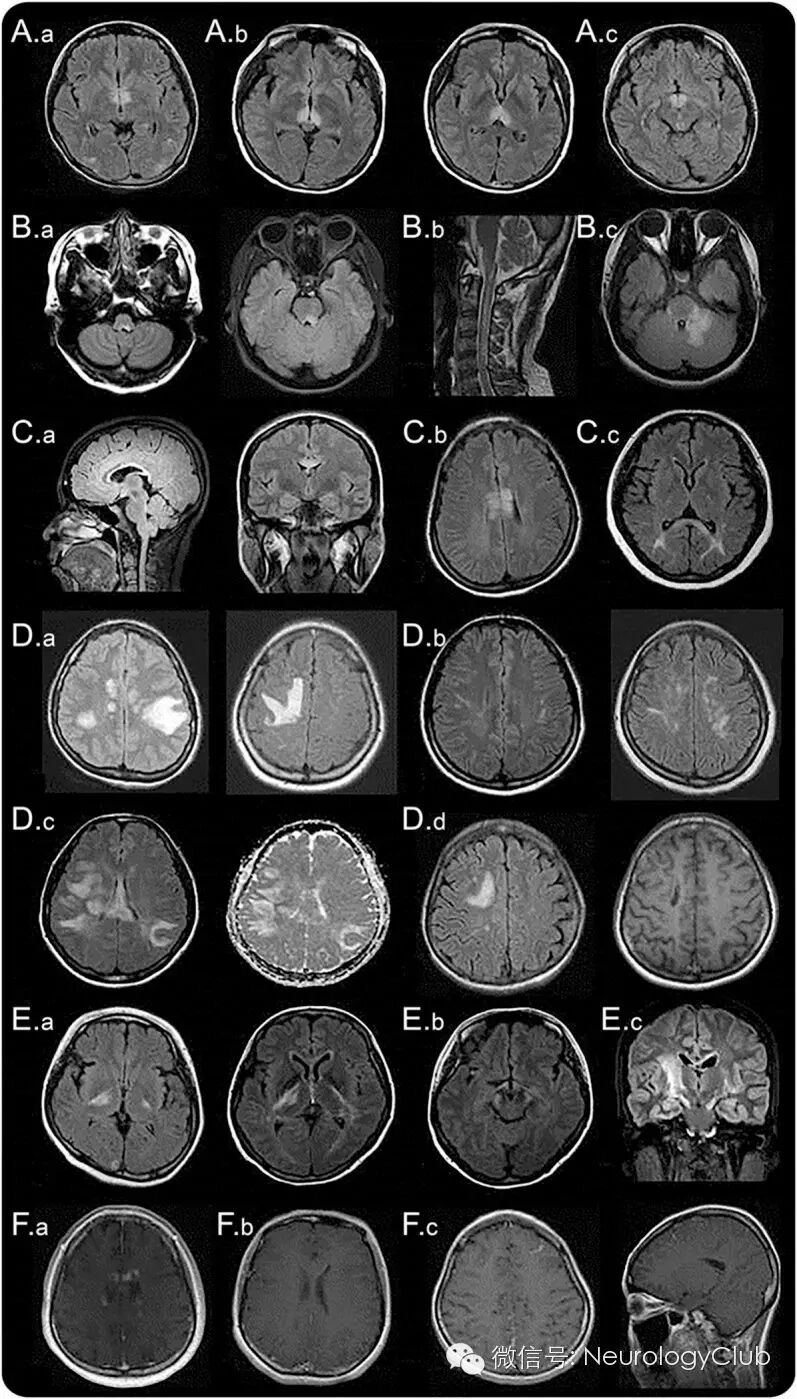

(1)环绕第三脑室和导水管的间脑病变:环绕第三脑室和导水管的间脑病变部位包括丘脑、下丘脑、中脑前界,在NMOSD中已有报道(图1A)。这些病变通常是无症状的,但是有些患者可能会出现抗利尿激素分泌异常、嗜睡发作、低体温、低血压、睡眠过度、肥胖、甲状腺功能减退、高泌乳素血症、继发性闭经、溢乳和行为改变等症状。

(2)邻近四脑室的脑干背侧病变:邻近四脑室的脑干背侧包括极后区(area postrema)和孤束核的病变是NMOSD患者最为特异性的头颅MRI表现之一。见于7-46%的NMOSD患者,并且与顽固性呃逆、恶心、呕吐有高度相关性。这一区域为呕吐反射的中枢,有着较为疏松的血脑屏障,因而更容易受到AQP4-IgG的攻击。MRI和临床证据均提示极后区是NMOSD易受攻击的重要区域,后续研究发现该区域是血液循环中的IgG进入中枢神经系统的重要通道。40%的NMO患者这一区域有病理改变,但是没有明确的神经元、轴索或髓鞘缺失。延髓病变常与颈髓病变相连续,多呈线形(图1B.b)。这些病灶常与疾病的第一症状或者预示急性恶化有关。脑干病变可出现各种不同的临床表现,例如眼球震颤、构音障碍、吞咽困难、共济失调、眼肌麻痹等。

(3)环绕侧脑室的室管膜周病变:胼胝体病变见于12-40%的NMOSD患者。因为NMO和MS患者都常出现胼胝体病变,所以这一部位并不能作为NMO和MS的特异鉴别点。但是,MS的胼胝体病变常常是不连续的、卵圆形、垂直于侧脑室,多累及胼胝体下部(图2A)。而NMOSD病变位置与侧脑室很接近,紧贴室管膜内层(图1C.a)。NMOSD急性期的胼胝体病变常有明显水肿,且为多形性,形成“大理石样图案(marbled pattern)”,有时累及胼胝体压部全层,出现独特的“拱桥形图案(arch bridge pattern)”(图1C.b和C.c)。有时,胼胝体病变延续至大脑半球,形成广泛、融合的白质病变。在NMOSD的慢性期,胼胝体病变可逐渐缩小、信号减弱,甚至可以消失;但是,囊变和胼胝体萎缩都曾有过报道。某些临床表现,如认知功能和运动协调能力障碍等,可能与胼胝体受损有关,但证据并不是很充分。

2大脑半球的白质病变

广泛、融合的大脑半球白质病变常呈瘤样(最大半径可以>3cm),或者沿白质纤维走行呈长纺锤状或放射状(图1D)。通常无占位效应。ADC上病灶弥散系数增高,提示可能为急性炎症相关的血管源性水肿(图1D.c),可能与可逆性后部脑病综合征(PRES)或Balo病混淆。相较于AQP4抗体阴性的患者,这些广泛的病变在AQP4抗体阳性的患者中更常见。疾病慢性期,这些大病灶趋向于缩小甚至消失,但有一些患者可出现囊样或空洞型改变。上述病变根据其累及区域的不同可引起各种症状,如偏瘫、脑病、视野缺损等。大片融合的大脑半球白质病变在NMOSD患儿中比较常见。伴随着灶周水肿和不同程度占位效应的肿瘤样病灶可类似急性播散性脑脊髓炎(ADEM)或中枢神经系统恶性肿瘤。

3病变累及皮质脊髓束

皮质脊髓束受累可为单侧或双侧,病灶可能从大脑半球深部的白质通过内囊后肢延伸至中脑的大脑脚或者脑桥(图1E)。这些病灶连续,常为长节段,沿锥体束分布(图1E.c)。一些关于NMOSD患者的队列研究报道,约23-44%的患者存在皮质脊髓束的病灶,在其他研究中也偶有发现。有意思的是,和脑室周围不同,皮质脊髓束并不是AQP4高表达的区域,因此目前尚不清楚NMOSD患者这一区域常累及的原因。

4非特异性病灶

T2WI/FLAIR上,皮质下区或深部白质区常可观察到非特异性的小点状(<3mm)或片状高信号,这是NMOSD最常见的头颅MRI异常(35-84%),通常无临床症状。

5强化病灶

先前的一些研究报道9-36%的NMOSD患者头颅MRI可出现强化病灶,但具体比例尚不清楚。大多数病灶呈边界不清、模糊的多发片状强化,即所谓的“云雾状强化”(图1F.a)。这种云雾状的强化模式有助于与边界清楚的卵圆形或环状/开环状病灶(图2)鉴别,后者为MS较为典型的特征。侧脑室室管膜表面的线状强化(铅笔样病灶)也有报道(图1F.b)。边界清楚的结节样强化或脑膜强化也可见于NMOSD患者,但罕见。

(Aa:环绕第三脑室和导水管的间脑病变;Ab:丘脑、下丘脑受累;Ac:中脑前界;Ba:邻近四脑室的脑干背侧病变;Bb:与颈髓病变相连续的延髓线状病变;Bc:肿胀弥漫的脑干背侧病变,累及小脑脚;Ca:邻近侧脑室、紧贴室管膜内层的胼胝体病变;Cb:胼胝体病变呈“大理石样图案” ;Cc:胼胝体病变呈“拱桥形图案”;Da:肿瘤样大脑半球白质病变;Db:长纺锤状病灶;Dc:ADC上病灶弥散系数增高,提示血管源性水肿;Dd:慢性期大脑半球病灶囊性变;Ea:内囊后肢皮质脊髓束病变;Eb:中脑大脑脚病变;Ec:沿锥体束的长节段病变;Fa:云雾状强化;Fb:侧脑室室管膜表面线状强化;Fc:脑膜强化)